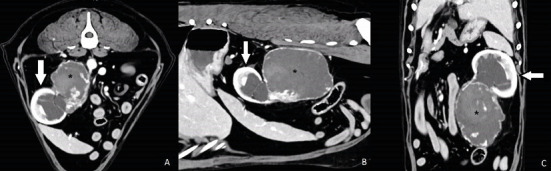

A dog (neutered male, 11 years old, Labrador retriever) underwent abdominal ultrasound, which revealed a 7 cm diameter tumour (caudal region of the left kidney). The animal showed symptoms of weight loss, apathy, haematuria, and abdominal pain. A computed tomography (CT) scan confirmed the presence of a tumour originating from the ureter. Following surgery to remove the ureter with the attached kidney, a histopathological examination was performed. The tumour was classified as a haemangiosarcoma. After the initial recovery, 2 months after surgery, the dog was diagnosed with a tumour in the other kidney. A fine needle biopsy was carried out. A haemangiosarcoma metastasis was suspected. Neoplasms of the ureter are a rare pathology. This is the first case in which metastasis to the second kidney has been confirmed.